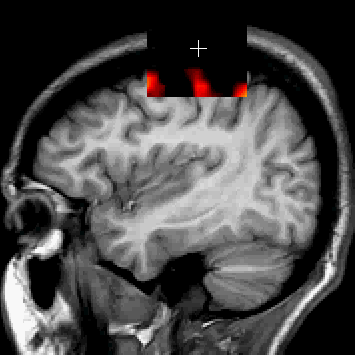

Two scans of the same patient can displayed as seperate images, but it may be more useful to the researcher to view the images together. This view -- where the underlying image is all or partly invisible except when viewed by the window, allows a researcher to focus on one image, while picking the second image data when need be. The image at right displays the sMRI data displayed with the window cursor, and is displayed over the functional MRI. Otherwise, the sMRI is invisible.